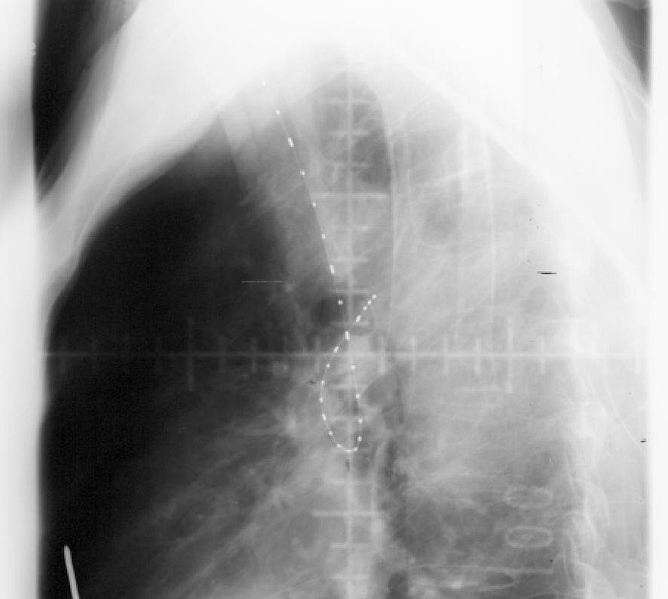

X-ray of person’s body undergoing endobronchial radiation therapy. | wikimedia/Tdvorak

Radiating energy is known as radiation, while radioactivity is a specific type of radiation: the production of electromagnetic particles during nuclear decay. When we get an x-ray or a CT Scan, our body is exposed to radioactivity.